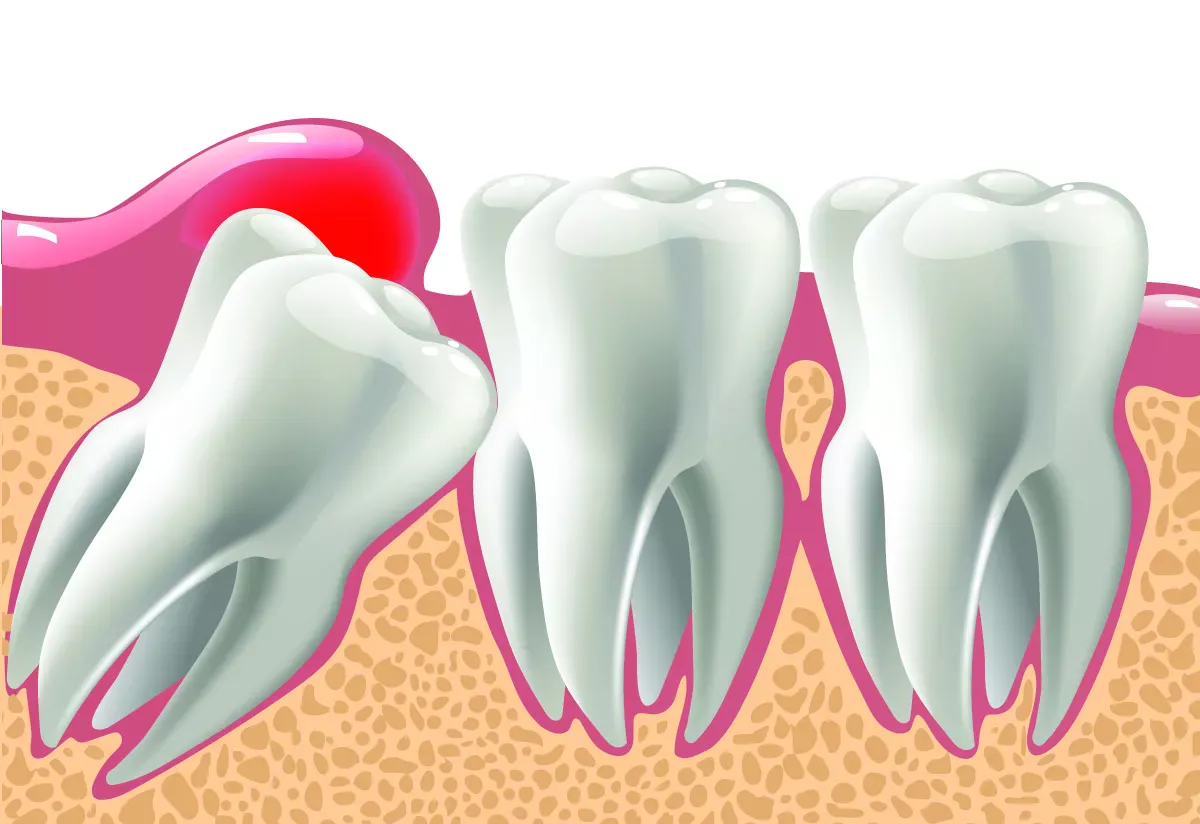

Partially retained wisdom teeth

If wisdom teeth try to break through when there is actually no room in the mouth, this can cause severe pain. The wisdom tooth then not only presses against the gum that stretches over it, but also against the neighbouring tooth. It can happen that the neighbouring molar tooth hurts terribly, even though there is no caries or root inflammation. This is referred to as a "partially retained wisdom tooth": The tooth is still partially under the gum and cannot break through. A kind of gum cap often forms over the tooth. This cap can become inflamed very easily because it is difficult to reach with a toothbrush and provides an ideal breeding ground for bacteria.

Impacted wisdom teeth

If the wisdom teeth do not grow into the mouth at all, but remain in the jaw, they are referred to as "impacted wisdom teeth". People with impacted wisdom teeth often have no symptoms. However, if the wisdom tooth sits at an angle in the jaw and presses on a neighbouring tooth, it can damage the tooth. This can result in root caries, bone loss in the jaw or the teeth shifting due to the pressure.

Cysts can also form on impacted wisdom teeth, which the dentist can recognise on an X-ray. Cysts are filled with fluid and do not initially cause any pain. However, if they become inflamed, they can cause a feeling of pressure and dull pain.